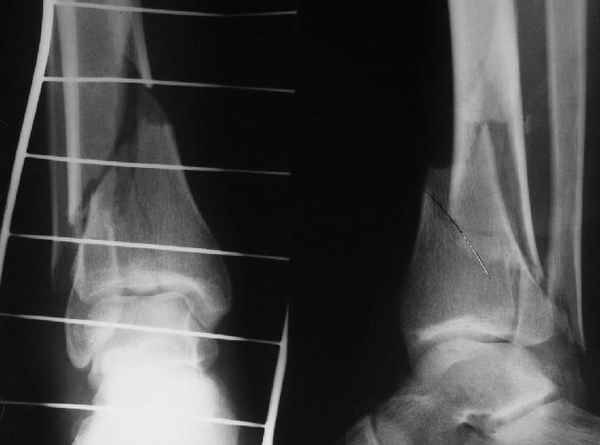

Да и нет! Зависит от перелома и способа остеосинтеза. А результат? (01)

А.Миронов

Кликните для загрузки файла 01.jpg

Мы же говорили о проксимальном плече. При переломе tibia, конечно, речи о двух Y-спицах нет. Еще раз о них - пружинящая подвижность без "срезающих" перемещений фрагментов - дополнительный стимул к образованию периостальной мозоли.

А в данном случае - у нас был бы применен locked nail с еще меньшими дырочками на коже и с возможностью полной нагрузки немедленно после операции. Какие тут аргументы в пользу выбора пластины, а не интрамедуллярного гвоздя?